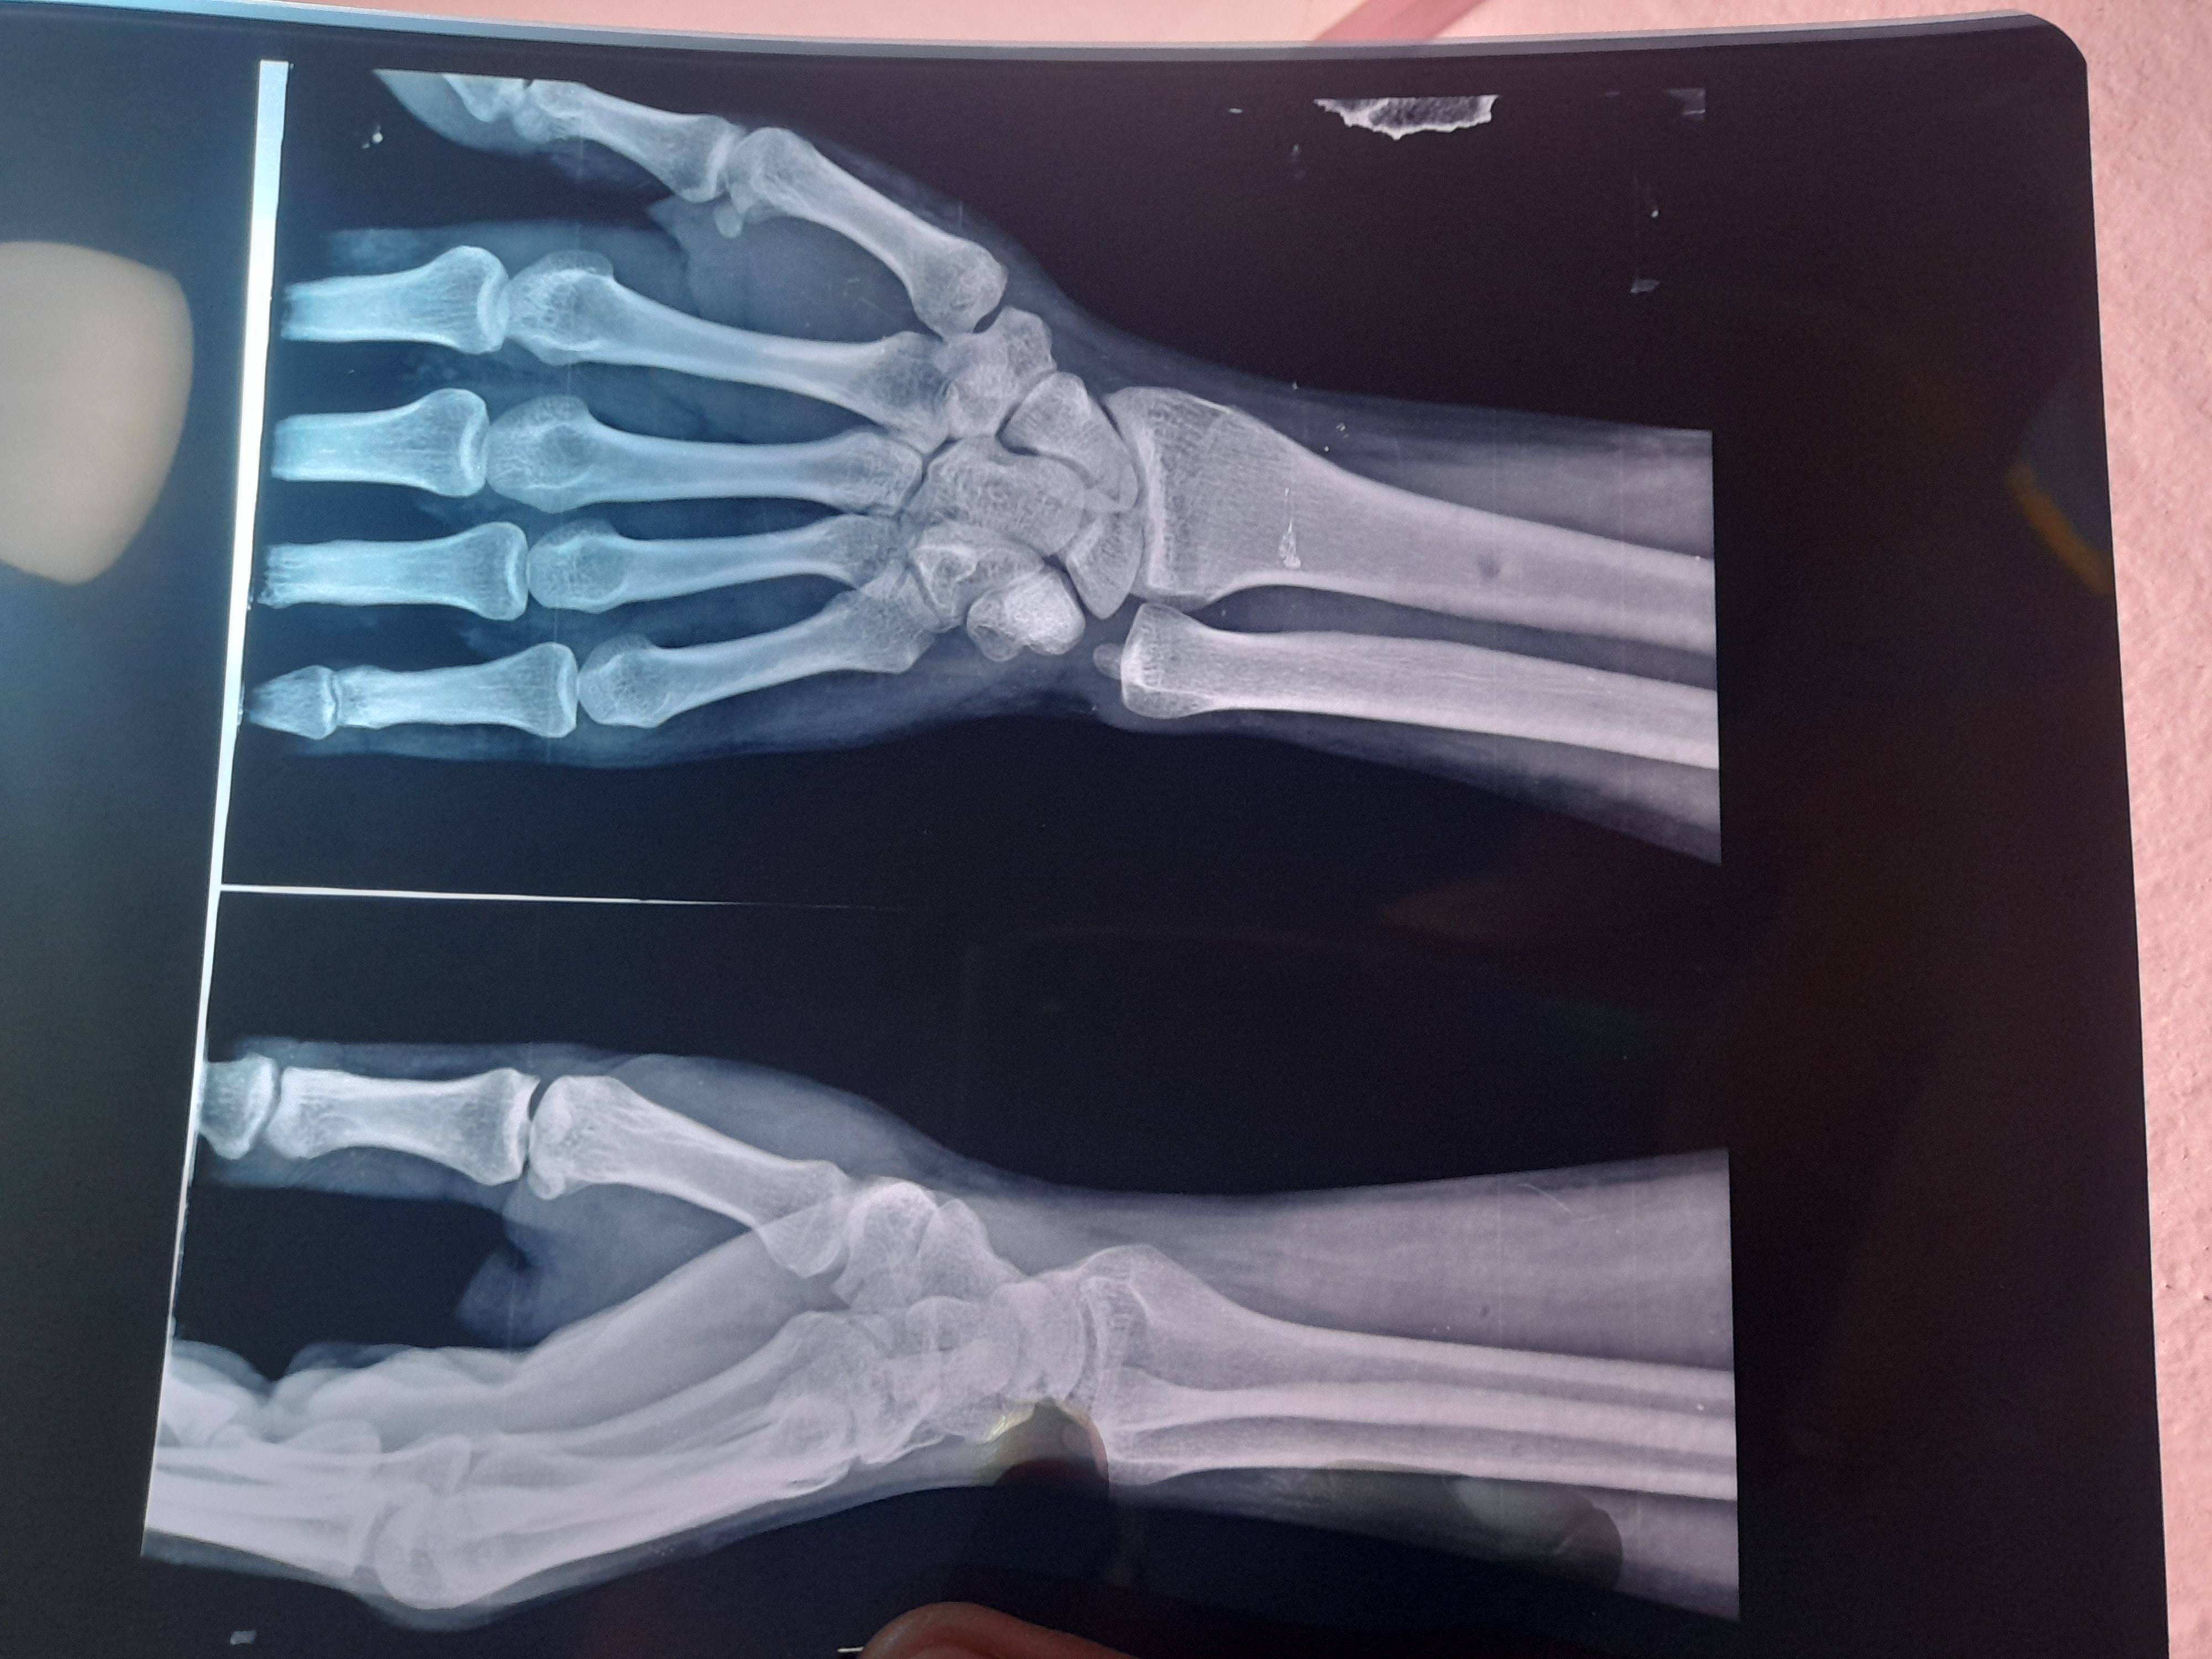

Nonunion Scaphoid right wrist

Dr. Ji muze 2014 me right wrist ko chot lagi thi tab Maine x-ray nikala tha lekin us time mere gaon ke orthopaedic dr. Ne bola ki thodi swelling hain 15 days tablet kha lo thik hoga 15 day after fir dikhana aise karte 30 day goli khai aram mila lekin 6 month after cloudy manson ke time fir se dard suru huva main dusare dr ke pas gaya unhone bhi x-ray nikala aur bole nonunion scaphoid hain MRI karna padega uske bad MRI nikala dr. Bole philhal opration ki jarurat nahi hain jab jada dikkat hogi to karenge lekin ab 2023 8 years after muze right wrist ko swelling aur bahut dard ho raha hain kya karu arthritis ke lakshan dikhne lage hain lekin RA antibiotics ke test negative hain CRP 61 hain